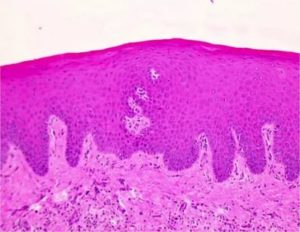

Лейкоплакия вульвы является основным проявлением плоскоклеточной гиперплазии — дистрофического заболевания вульвы с поражением многослойного плоского неороговевающего эпителия.

При лейкоплакии вульвы наблюдается появление в норме отсутствующих в эпителии рогового и зернистого слоев, развитие пара- и гиперкератоза, акантоза (без клеточной и ядерной атипии или с атипией).

Гиперкератоз — это состояние поверхностного слоя кожи, выражающееся в увеличении количества кератиновых клеток рогового слоя эпидермиса без изменения их строения, приводящее к утолщению кожного покрова пораженной области. При гиперкератозе кожа теряет эластичность, становится малорастяжимой (ригидной), снижается ее чувствительность к внешним раздражителям.

Гиперкератоз – патологическое утолщение рогового слоя эпидермиса. Он возникает в том случае, когда клетки крайнего слоя делятся с большой скоростью, а отшелушивание ороговевших клеток, наоборот, замедленно. Вследствие этого и происходит уплотнение участков кожи.

Гиперкератоз – это патология кожи, которая характеризуется чрезмерной скоростью деления клеток рогового слоя и одновременно нарушением их слущивания. Сам термин является симбиозом двух греческих слов – hyper («много») и keratosis («кератин»).